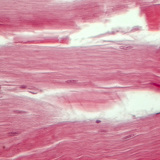

تكبير 400 مرة

علم الأحياء